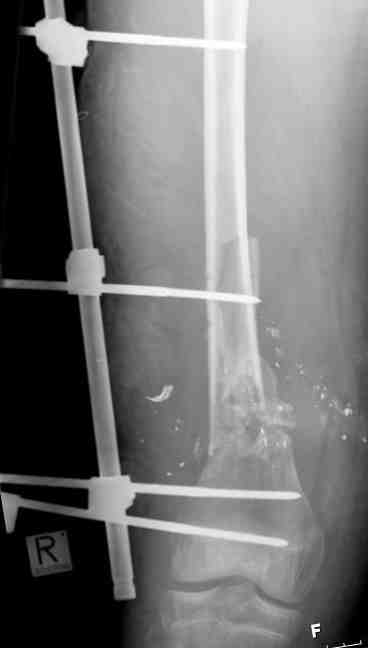

Выше приведены рентгенограммы 13-летнего подростка, страдающего от огнестрельного многооскольчатого перелома дистальной трети бедра. AO наружный фиксатор наложенный в день травмы не дал приемлемой редукции. Через три недели после перелома аппарат Илизарова был наложен без попытки одномоментной репозиции на операционном столе. There are X-Rays of a thirteen year old boy with a comminuted distal femur fracture secondary to a gunshot wound, initially treated with an AO external fixator. The alignment was unacceptable and an Ilizarov external fixator was applied three weeks after the injury. No attempt of definitive reduction was made during the surgery.

Гексаподная приставки наложена на 10 дней и приемлемая редукция была получена. The Hexapod set was applied for ten days and acceptable reduction was received.

По окончанию редукции Гексаподный сет был снят и дальнейшее ведение больного проходило в стандартном режиме аппарата Илизарова. Хороший анатомо-функциональный результат был получен. When reduction was finished, the Hexapod set was removed and further management has been continued by standard Ilizarov regime. Good anatomic and functional results were achieved.